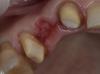

Art 7 Опубликовано 25 марта, 2013 Поделиться Опубликовано 25 марта, 2013 ситуация до,небольшой пролежень от поломанного временного мостиканемного анестезии, немного алмазов,немного гемостатикаотжал времянку, добавил жидкотекучего,обработалфиксация с небольшой компрессией 5 Ссылка на комментарий